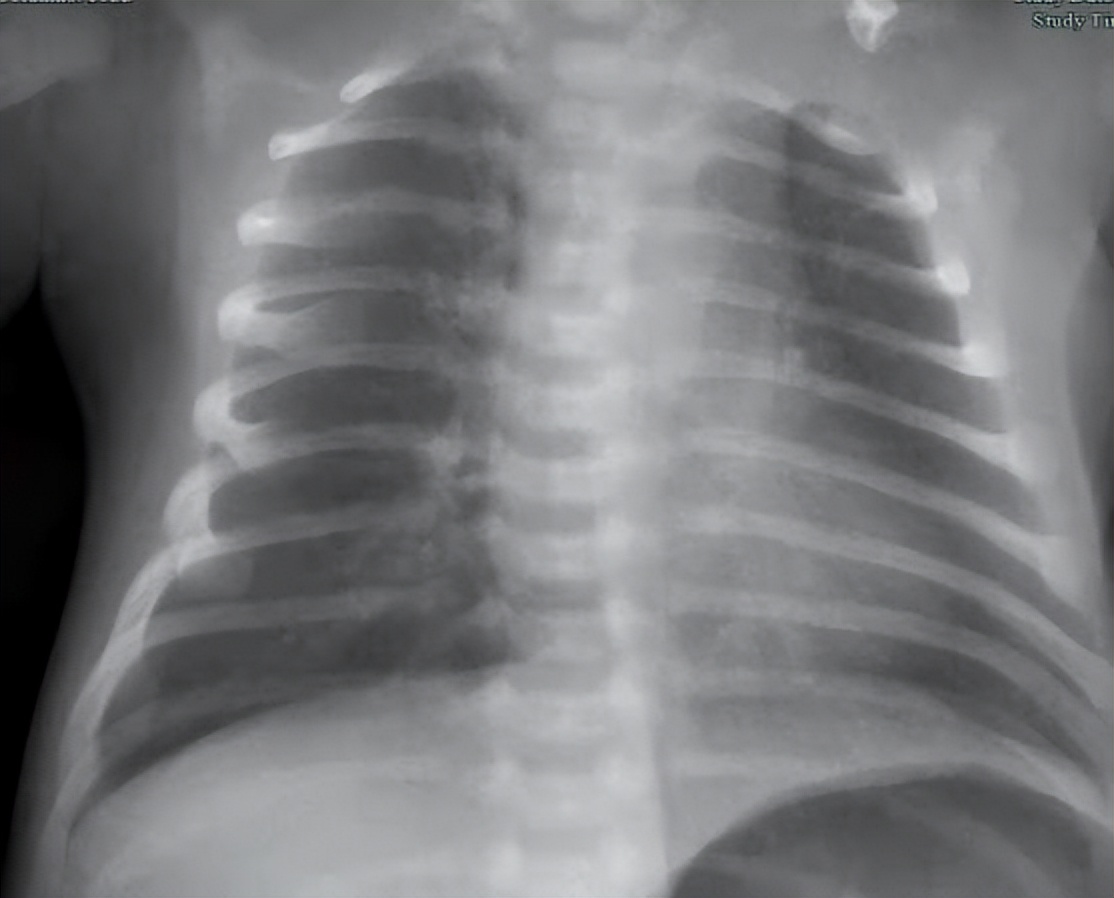

患儿入院后,基于“新生儿肺炎”的考虑,进一步完善胸片,血常规+CRP,血凝常规,血型检测,血气电解质乳酸CO分析,尿常规等相关检查。这些检查是为了进一步确诊患儿是否是新生儿肺炎,从而排除其他误诊。检查结果示患儿双肺有散在模糊影,白细胞增多,血红蛋白增多,CRP全血快速定量<1mg/L,血型Rh阳性,血型为O型,尿比重正常,尿中葡萄糖,蛋白质,红细胞阴性。

经过住院治疗后,患儿咳嗽次数减少,鼻部呼吸通畅,睡眠佳,复查血常规,白细胞恢复正常,胸片模糊影减少。

经住院治疗8天,患儿精神状态佳,无明显咳嗽,无鼻塞,喉间痰鸣少许,无喘息气促,无呼吸暂停,无发热,无少吃少动少哭,无尖叫抽搐,大便偏稀,小便无特殊。进一步复查患者白细胞恢复正常,胸片模糊影减少。查体咽无充血,双肺呼吸音粗,未见明显干湿啰音。